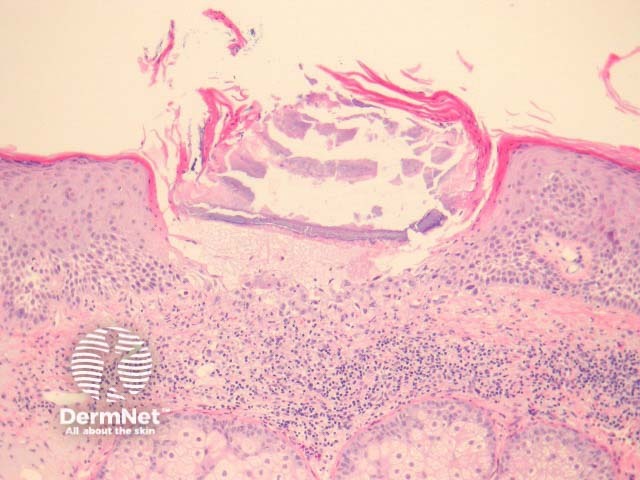

In necrotising infundibular crystalline folliculitis, sections show filamentous deposits, enclosed by parakeratotic columns within partly necrotic follicle ostium (figure 1). There is incidental actinic keratosis in the case illustrated herein. Higher power examination shows crystalline urate-like structures within the filamentous material (figures 2, 3). The material is birefringent with polarised light.

Figure 1